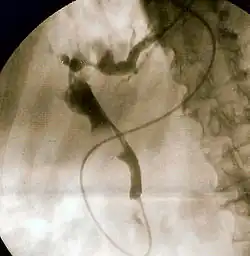

Endoscopic retrograde cholangiopancreatography (ERCP) is a technique that combines the use of endoscopy and fluoroscopy to diagnose and treat certain problems of the biliary or pancreatic ductal systems. It is primarily performed by highly skilled and specialty trained gastroenterologists. Through the endoscope, the physician can see the inside of the stomach and duodenum, and inject a contrast medium into the ducts in the biliary tree and/or pancreas so they can be seen on radiographs.

The patient is sedated or anaesthetized. Then a flexible camera (endoscope) is inserted through the mouth, down the esophagus, into the stomach, through the pylorus into the duodenum where the ampulla of Vater (the union of the common bile duct and pancreatic duct) exists. The sphincter of Oddi is a muscular valve that controls the opening to the ampulla. The region can be directly visualized with the endoscopic camera while various procedures are performed. A plastic catheter or cannula is inserted through the ampulla, and radiocontrast is injected into the bile ducts and/or pancreatic duct. Fluoroscopy is used to look for blockages, or other lesions such as stones.[8][9]

When needed, the sphincters of the ampulla and bile ducts can be enlarged by a cut (sphincterotomy) with an electrified wire called a sphincterotome for access into either so that gallstones may be removed or other therapy performed.[10]

Other procedures associated with ERCP include the trawling of the common bile duct with a basket or balloon to remove gallstones and the insertion of a plastic stent to assist the drainage of bile.[11] Also, the pancreatic duct can be cannulated and stents be inserted.